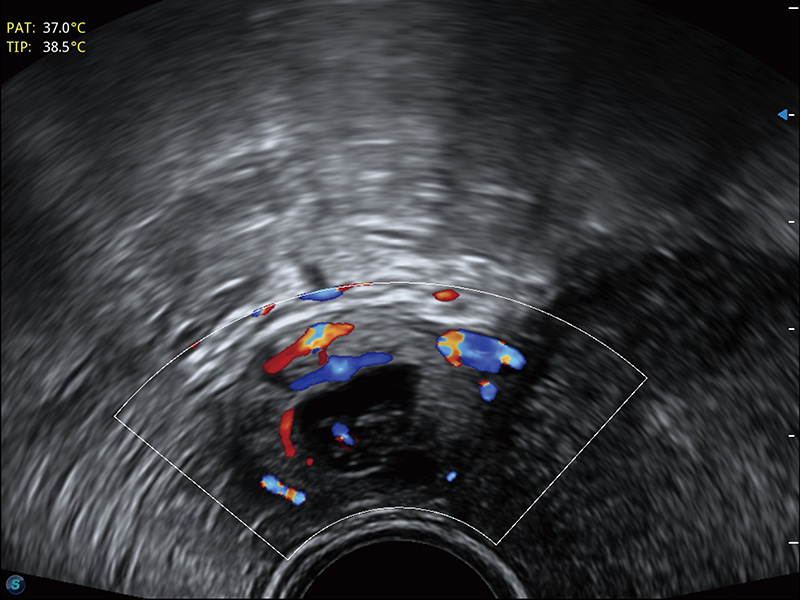

超声引导下双侧卵巢穿刺取卵

宫外孕血流